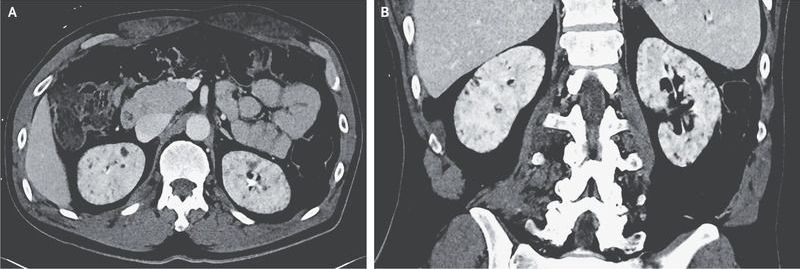

A 59-year-old man with a history of bipolar disorder was admitted to the hospital after a fall. He received a diagnosis of multiple fractures of the head and spine; the fractures were managed nonoperatively. During the hospitalization, his urine output was noted to range from 4 to 6 liters per day. The patient had taken lithium for 27 years before discontinuing the medication 8 years before the current presentation because of mild hyperparathyroidism and renal insufficiency (serum creatinine level, 1.5 mg per deciliter [130 μmol per liter]). While he was immobilized in the hospital, his serum sodium levels rose from 138 mmol per liter to 149 mmol per liter, with a urine osmolality that was inappropriately low (262 mOsm per kilogram). The urine osmolality did not increase with the administration of desmopressin, which confirmed a diagnosis of nephrogenic diabetes insipidus. As part of the evaluation for the fall, computed tomography of the abdomen and pelvis with contrast enhancement was performed, and the results showed numerous small renal cysts in the cortex and medulla of both kidneys (axial [Panel A] and coronal [Panel B] views, with a nonstandard window used to enhance visibility of cysts). Lithium is known to cause tubulointerstitial nephropathy, which may be seen on imaging as multiple small cysts. Management of this patient’s condition included a low-salt diet and a liberal intake of fluids. His sodium level normalized, and he was discharged to a rehabilitation facility.